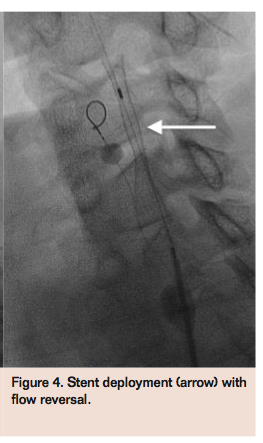

(Figure 3). An Xact 7-9 mm x 40 mm self-expanding stent (Abbott Vascular) was deployed in the left ICA extending into the CCA (Figure 4), and postdilated using a Viatrac 5 mm x 30 mm balloon (Abbott Vascular) with good expansion (Figure 5). Aspiration of debris was performed prior to deflating both the left ECA and CCA balloons. The ECA balloon wire and Prowater guidewires were withdrawn, and final angiograms confirmed excellent angiographic results with brisk flow through the left ICA (Figure 6) and preserved intracerebral flow. The patient was transferred to the intensive care unit for observation overnight and discharged home the following day on dual-antiplatelet therapy without any complications.